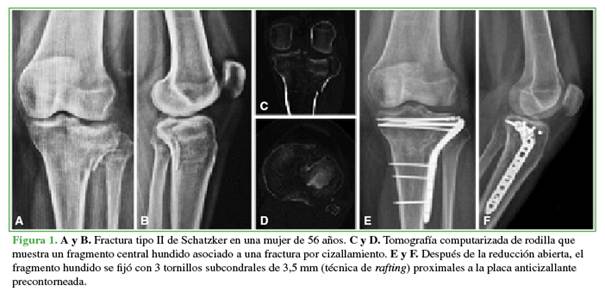

Tras la reducción, se procedió a la fijación preliminar con agujas de Kirschner. En el grupo con técnica derafting (Figura 1), la fijación definitiva se hizo con tornillos subcondrales de 3,5 mm a través de la placa cuando su diseño permitía una colocación adecuada de los tornillos subcondrales. En caso contrario, los tornillos se colocaron proximalmente fuera de la placa.